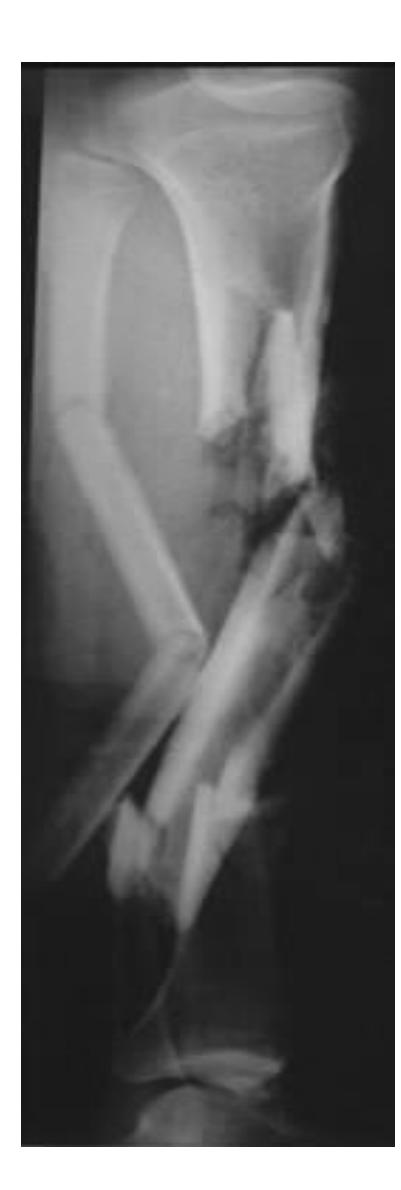

Tibial Fractures

Tibia and Fibula Fracture

Diagnosis: Segmental and comminuted fracture of tibia and fibula

Q1: What is the mechanism of this injury?

- Spiral fracture caused by indirect twisting injury

Q2: What is the treatment of choice?

- Surgical treatment is best

- Conservative options if minimally displaced: Long leg cast for 4-6 weeks, Patella-bearing cast (Sarmiento) or fracture brace

- Average union time is 16ยฑ4 weeks

- Operative treatment: Intramedullary (IM) Nailing is the treatment of choice